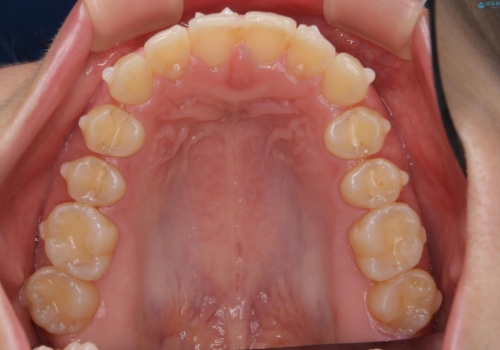

出っ歯に見える前歯の改善 部分ワイヤーとマウスピース矯正

- 出っ歯に見える前歯の改善を希望され、来院されました。

マウスピースでは改善の難しい歯の動きを部分ワイヤー矯正で整えたのち、奥歯の噛み合わせや細かい歯の並びをマウスピース矯正インビザラインで整えていきます。

最終的な前歯の並びに大変満足いただくことができました。